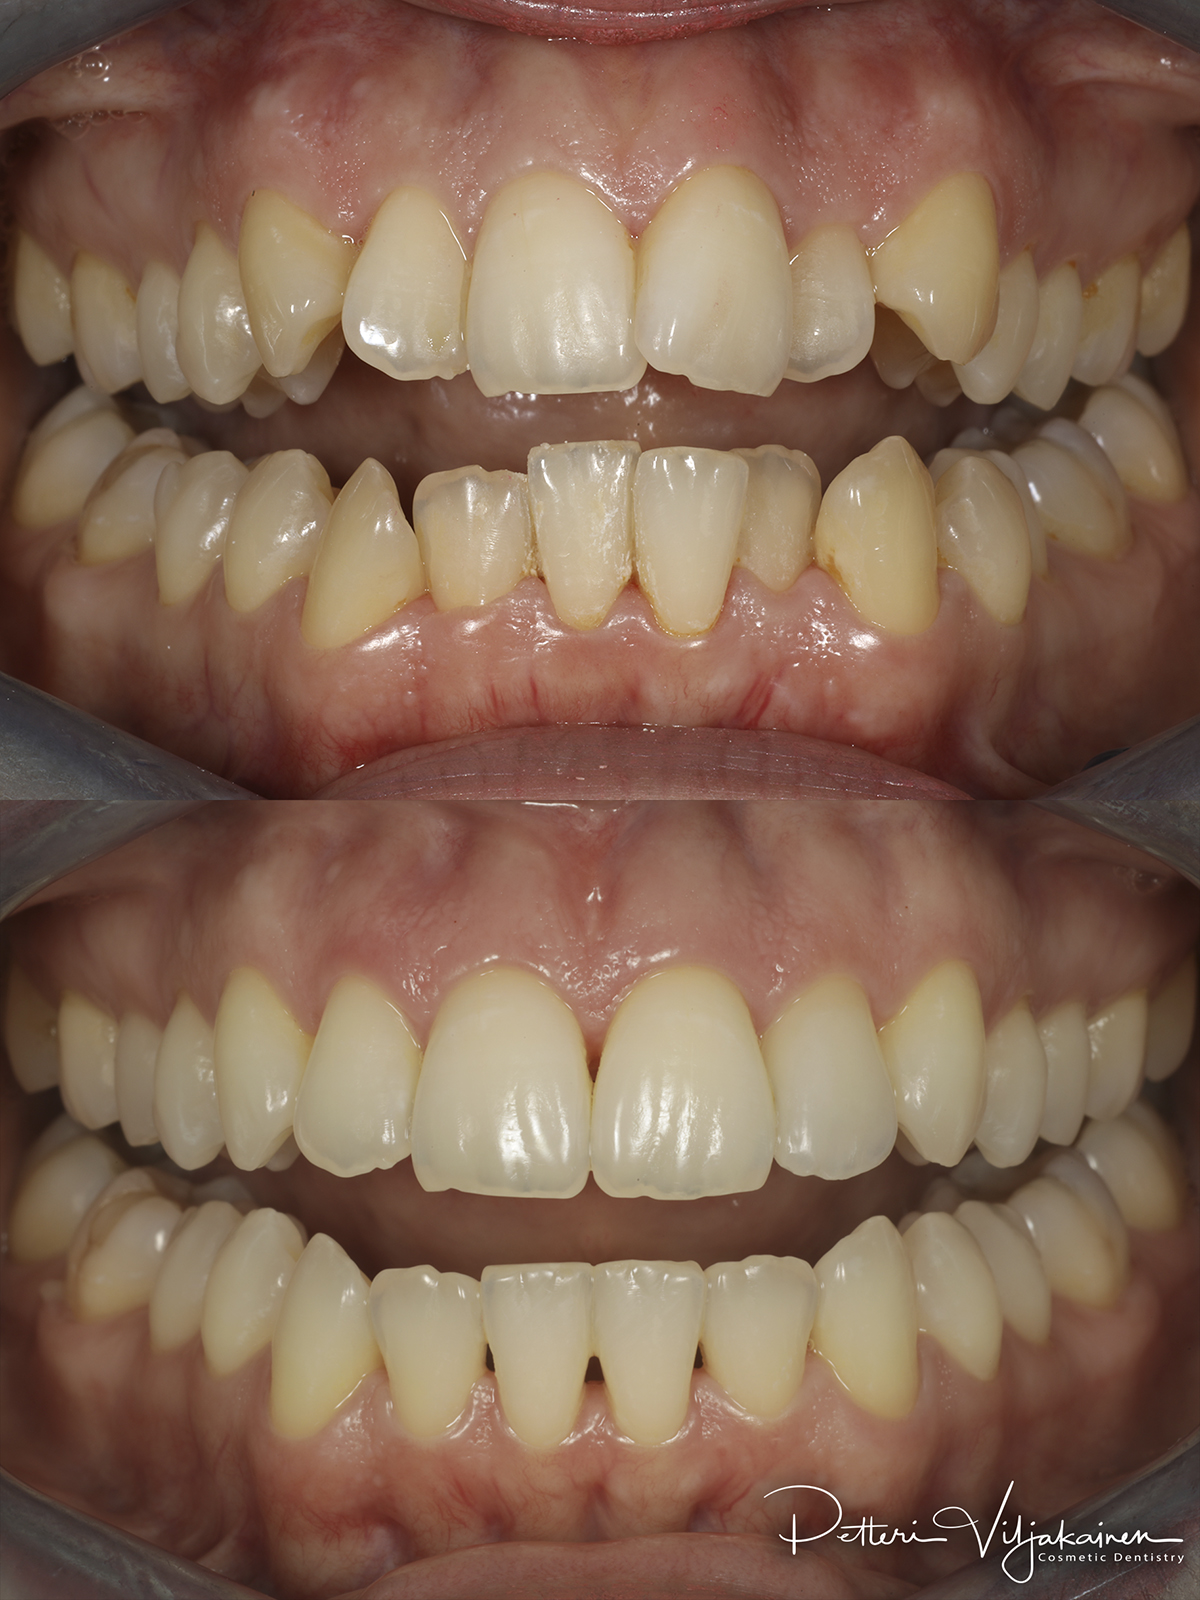

Alla suorittamiani hoitoja ja esimerkkejä siitä minkälaisia purentavirheitä voi korjata.

10kk hoito (Comprehensive). Etuhampaiden kärkien viimeistely kerrostusmuoveilla.